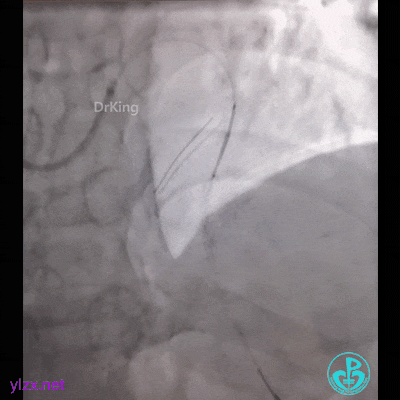

然而:锁骨下迷走,多次尝试TIG根本无法到位。

因为是心梗,患者持续胸痛,生命体征不稳,不再尝试,改腿。

然而,还是不能到位。